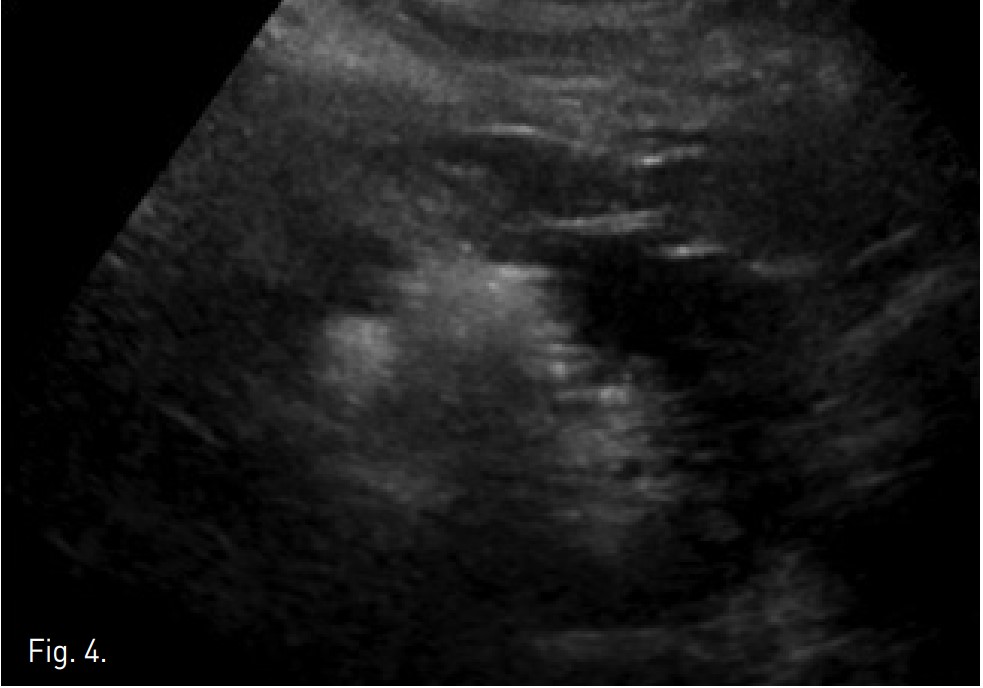

Fig. 4.

Fig. 4. On post-embolization US, RCC showed increased echogenicity and was RF ablated by using Radionics 3cm Cool-tip dectrode.

uptake가 보이고, emolization된 상태임 (Fig. 3B). 우측 신종양은 색전술 후 초음파에서 뚜렷이 증가된 에코음영의 종괴로 보였으며 (Fig. 4), Radionics 3cm Cool-tip electrode를 이용하여 고주파열치료를 12분간 시행하였음.